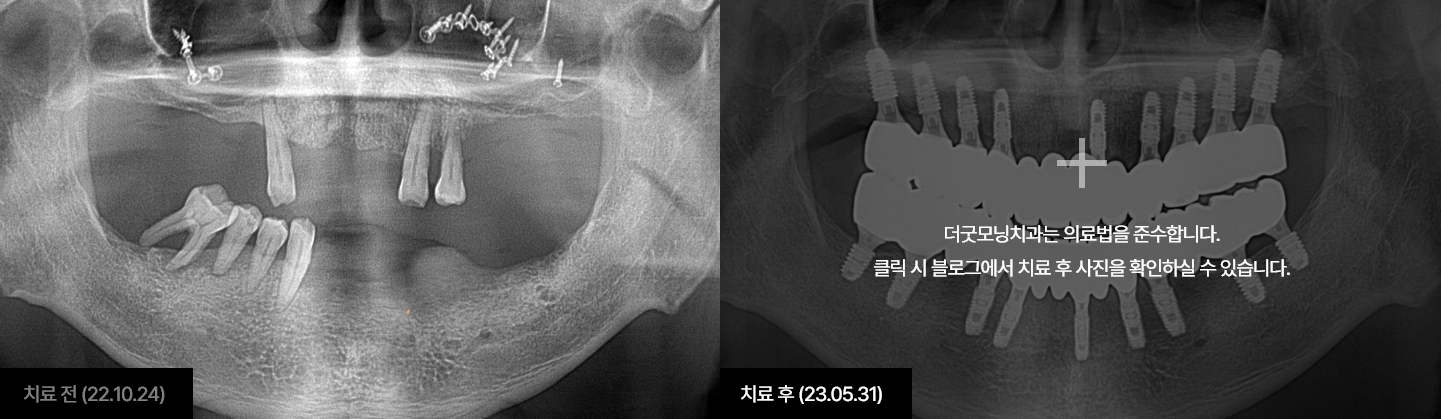

임플란트는 시술하는 의사의 수술 경험, 노하우에 따라 진료 결과가 달라지는

시술입니다.

잇몸뼈에 식립하여 자연치아를 대체해 주는 보철치료인 만큼

잇몸과

잇몸뼈에 대해 전문성이 높은 치주과 전문의가 진료해야 합니다.

더굿모닝치과는

보건복지부 인증 치주과+통합치의학과 더블보드 전문의가 직접 진료하며,

진단부터 식립, 최종 보철물까지 꼼꼼하게 완성해 드릴 것을

약속드립니다.

더굿모닝치과 블로그에서 해당 사례를 자세히 확인하실 수 있습니다.